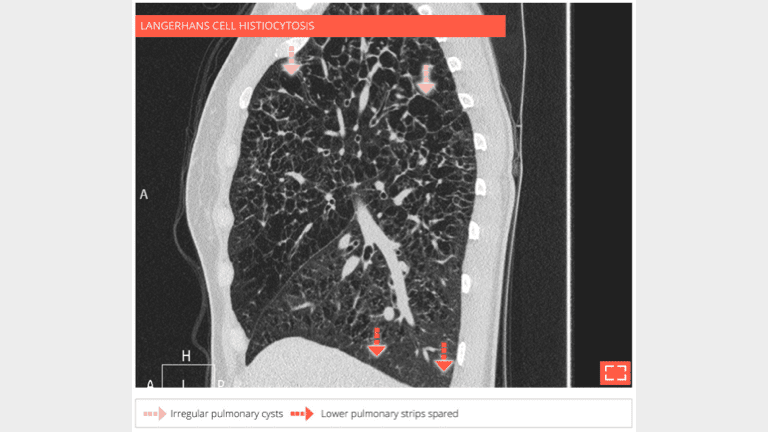

Sagittal reformation in the same patient shows the upper lobe distribution of parenchymal abnormalities

Sagittal reformation in a 58-year-old patient who was a former smoker and developed langerhans cell histiocytosis. HRCT shows large cysts with bizarre shapes.